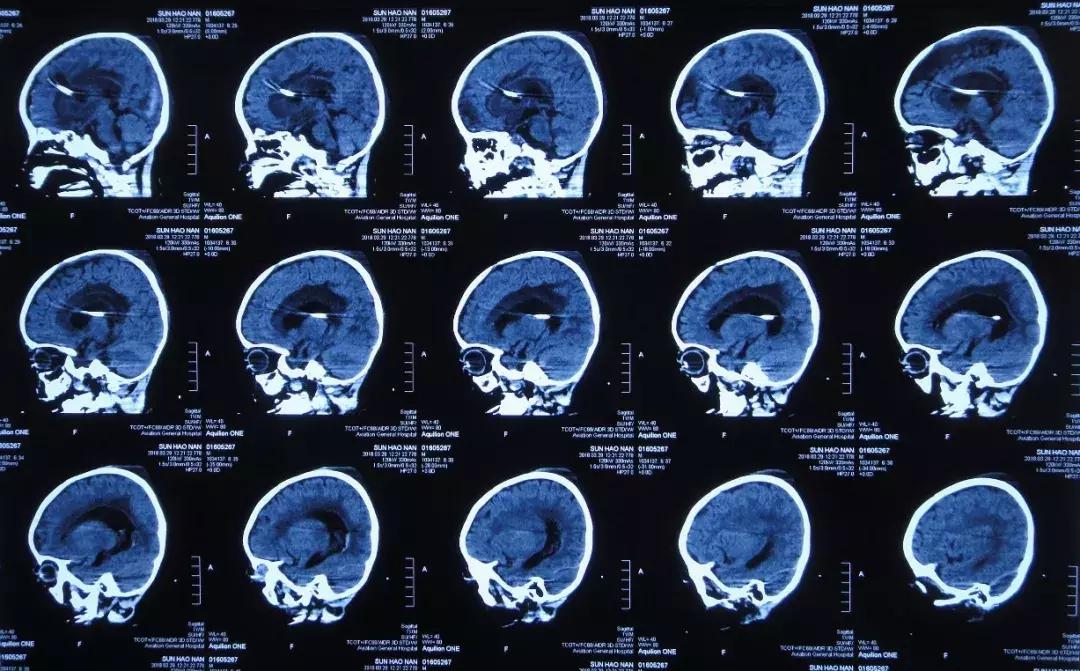

2018年2月25日头部影像检查

2018年1月30日小浩浩入住北京某儿童医院,医生给予抗感染治疗,2月7日复查头MRI:右侧积脓,中线左移,大脑多发环状异常信号,2月9日接受了经右枕侧脑室腹壁外引流术(有分流泵),引流的脑脊液细菌培养未检出细菌,患儿术后仍有间断发热,期间加用人免疫球蛋白,2月26日加用两性霉素B抗真菌治疗,疗程7天,患儿期间仍有发热,精神差伴呕吐。

2018年2月7日头MRI:右侧积脓